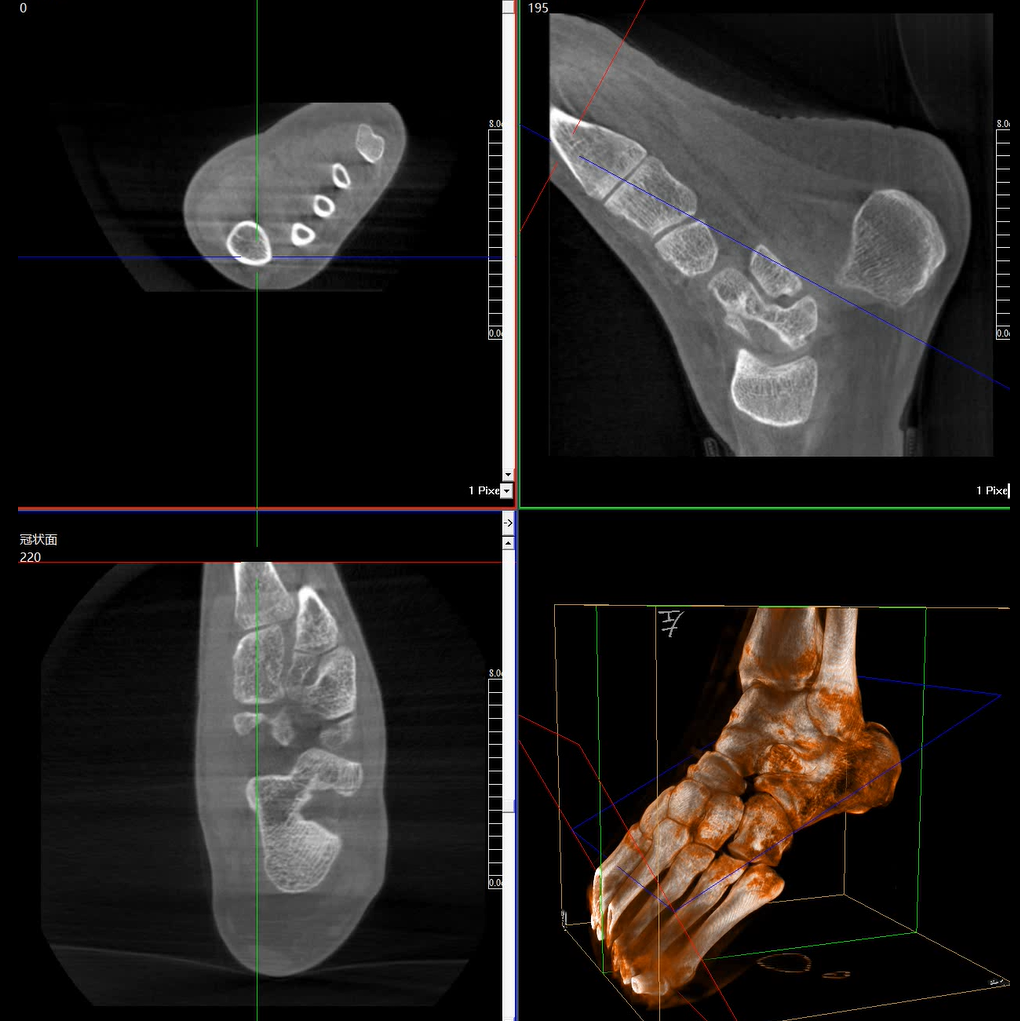

術(shù)中三維成像和橫斷面圖像提供多角度的手術(shù)診斷信息,輔助醫生進(jìn)行術(shù)中評估判斷,諸如骨折復位情況和內植入螺釘的尺寸和位置,輔助手術(shù)更好地完成。

提供更大的術(shù)中三維成像視野,采集更多圖像信息,可一次拍全全段頸椎、全段腰椎、七節胸椎、雙側骶髂關(guān)節、股骨頭及單側盆骨。